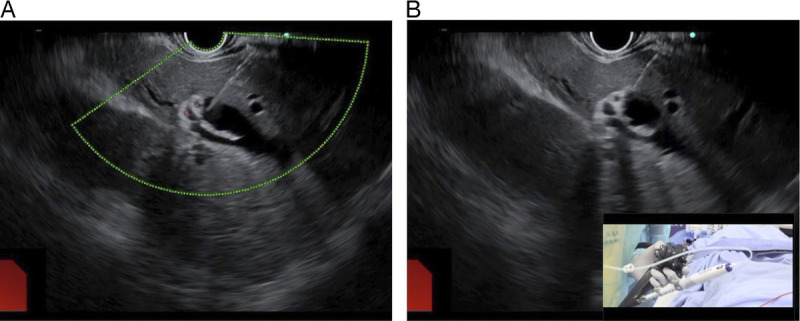

Technique tips for fitting alignment of puncture route during EUS-guided hepaticogastrostomy (with video).

在 EUS 引导下进行肝胃造口术时对准穿刺路径的技巧提示(附视频)。